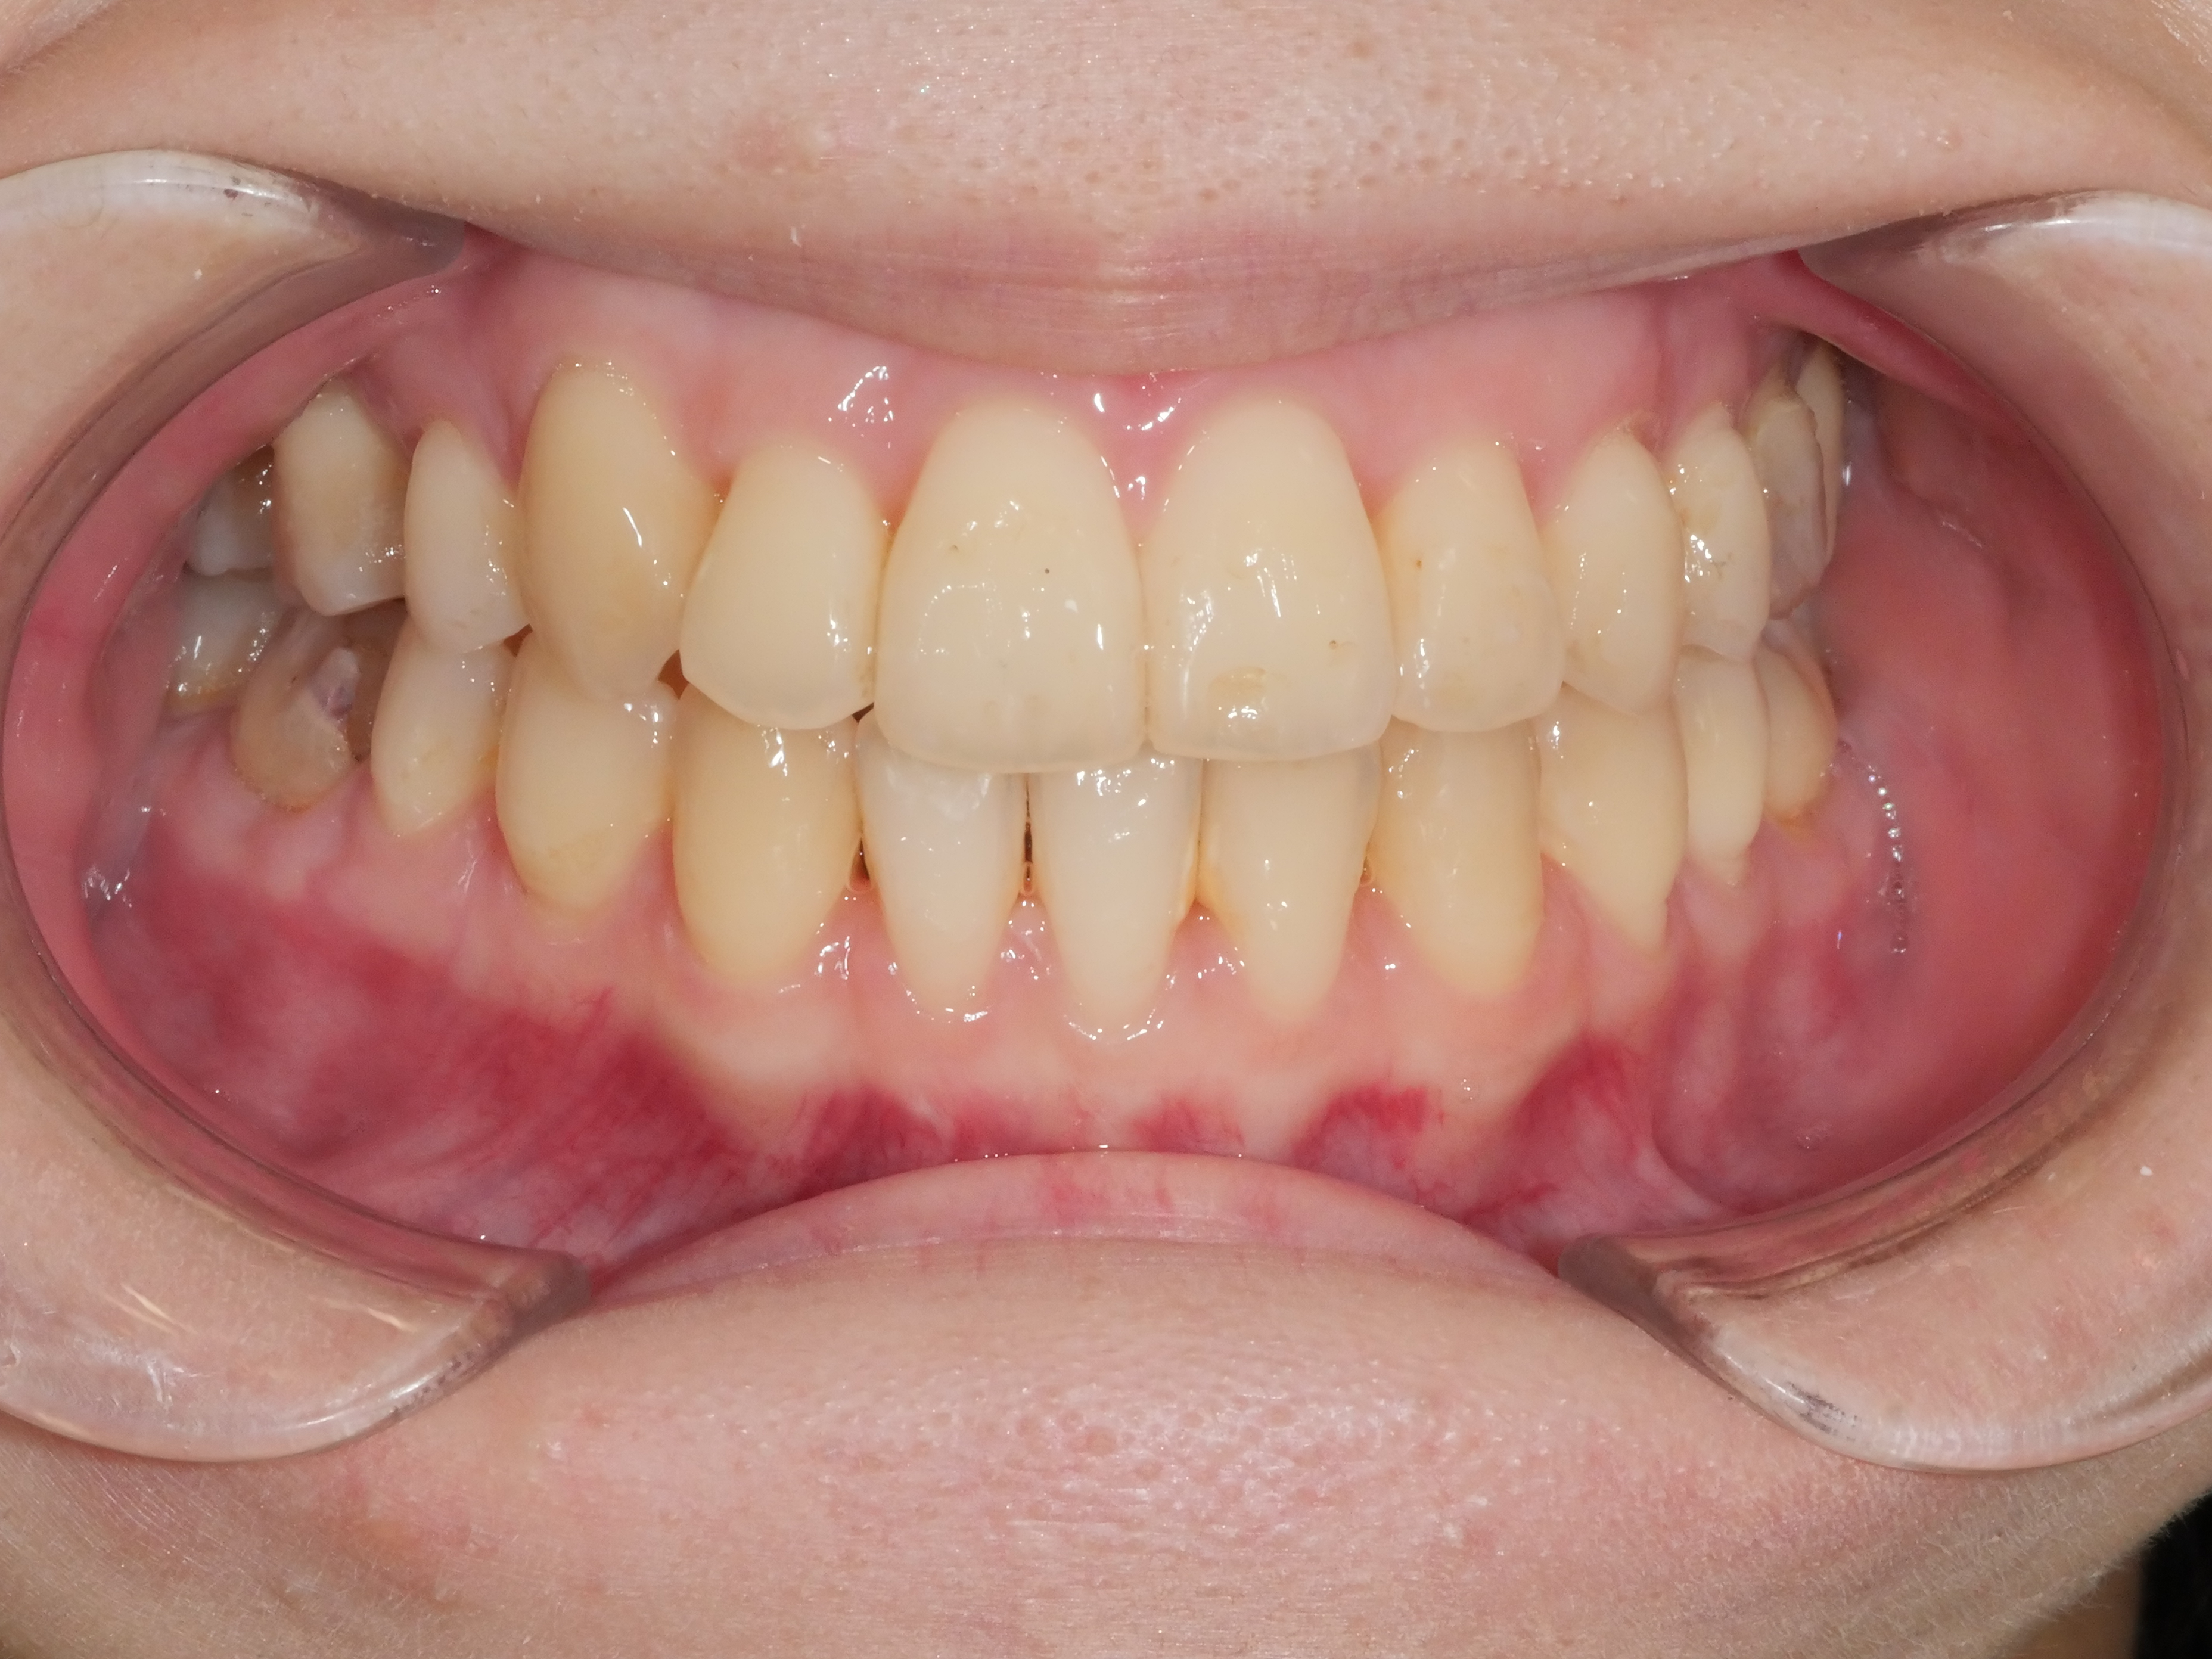

八重歯(ガチャ歯)を治したい

歯列が狭い・かみ合わせと凸凹

年齢層 20代(初診時)

性別 女性

主訴 【主訴】凸凹を治したい・上の歯が出ている 【診断・症状】叢生・交叉咬合

治療費用 検査・診断:38,500-/裏側矯正治療:1,375,000-(※全て税込)

治療期間 約2年3(24回)

抜歯 抜歯:有(上4,4)

矯正の装置 裏側矯正(舌側矯正)+QH

副作用、リスク 歯肉退縮・歯根吸収・疼痛・咬合の違和感・装置の違和感

before

after